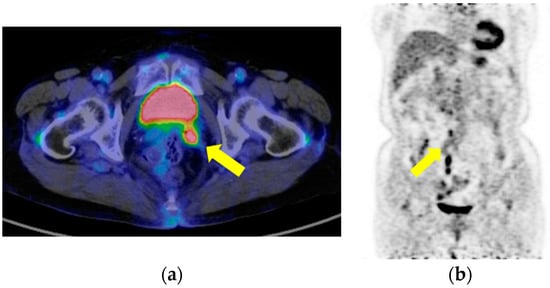

2. Case Presentation